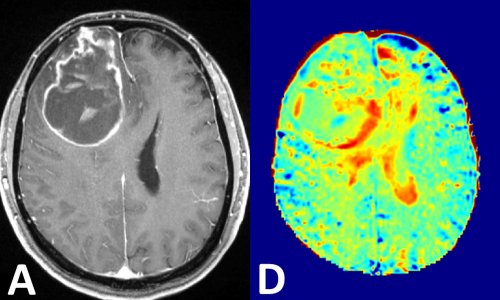

Bei der Hyperpolarisations-MRT wird die Ausrichtung der Kernmagnete künstlich so stark erhöht, dass eine vieltausendfache Signalverstärkung entsteht. Dieses magnetisch markierte (hyperpolarisierte) Kontrastmittel wird in den Körper eingebracht und sendet von dort Signale aus, die wesentlich stärker sind, als sie bei einer klassischen MRT möglich wären. Auf diese Weise lassen sich in Echtzeit molekulare Vorgänge detektieren. Den Weg von Molekülen in vivo nachzuverfolgen bedeutet nichts anderes, als Stoffwechselvorgänge abzubilden. „Das Versprechen der Hyperpolarisierung ist, dass man dem Leben an sich beim Arbeiten zugucken kann“, erklärt Hövener. Natürlich können auch krankhafte Stoffwechselvorgänge abgebildet werden, etwa bei Krebserkrankungen.

„Wir arbeiten nun intensiv daran, SAMBADENA auf Biomoleküle anzuwenden, die natürlicherweise im Körper vorkommen, um deren Ab- oder Umbau in Echtzeit beobachten zu können“, berichtet der Experte. Da Krebszellen häufig einen veränderten Stoffwechsel aufweisen, könnte ein verstärkter oder verminderter Abbau des Kontrastmittels auf Tumorgewebe hindeuten. Dadurch ließen sich Metastasen früher detektieren und Tumore genauer charakterisieren. Ebenso möglich scheint es, anhand der Veränderung des Krebsstoffwechsels frühzeitig zu erkennen, ob eine Therapie anschlägt oder nicht. Als Anwendungsbeispiel nennt Hövener Pyruvat: Dieses Biomolekül wird zu Lactat verstoffwechselt. Dazu braucht es das Enzym Lactat-Dehydrogenase, das sich oft in erhöhten Mengen in Tumoren findet. Hyperpolarisiert man also Pyruvat und führt es dem Organismus zu, wird dies im Tumor verstärkt in Laktat umgewandelt. So kommt man Konzentrationen von Lactat-Dehydrogenase, und damit möglichen Tumoren, auf die Spur.

„Dieses Verfahren ist um viele Tausend mal sensitiver als die klassische MRT“, schwärmt Hönever: „Das ist wie eine visuelle Biopsie.“ Zwar ist die Halbwertszeit der polarisierten Kontrastmittel – sie liegt im Bereich von mehreren zehn Sekunden – eher gering, doch glücklicherweise sind ausgerechnet Tumoren besonders schnell beim Verstoffwechseln. „Deshalb scheint die Hyperpolarisations-MRT eine geeignete Diagnosemethode für Tumoren zu sein“, bekräftigt der Freiburger Wissenschaftler.